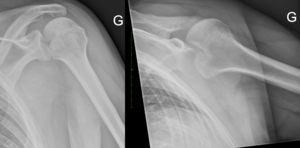

Magnetic Resonance Arthrogram (MRA)

Contrast enhancement during magnetic resonance arthrogram (MRA) is of great value and will increase the sensitivity of magnetic resonance imaging (MRI) in identifying a soft tissue injury (cartilage, rotator cuff, labral tears (Figure), a patulous capsule (Figure), reverse humeral avulsion of the glenohumeral ligaments (rHAGL, Figure), associated findings such as paralabral cysts) (Figure).

Computed Tomography (CT) Scan

Computed tomography (CT) scans also help the physicians to analyze the bony morphology of the shoulder joint. Before operative management, it is effectively imperative to assess for abnormalities in glenoid version (mean, 4.9 degrees in normal shoulders)[20] according to the Friedman technique,[21] posterior glenoid rim fractures or bone loss, and reverse Malgaigne (Hill-Sachs) lesions. These factors help determining the treatment strategies.